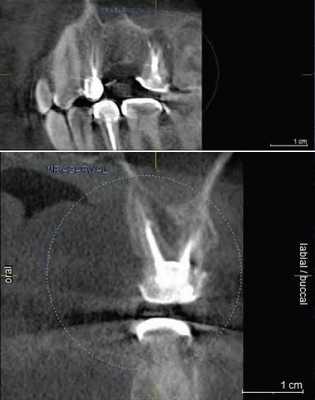

Резорбция корня это утрата твердых тканей зуба в результате активности остеокластов. Это может происходить в рамках физиологического или патологического процесса. Корневая резорбция может быть классифицирована на внешнюю и внутреннюю, в зависимости от локализации процесса относительно поверхности корня. Первые данные о внутренней резорбции получены в 1830. В сравнении с внешней резорбцией внутренняя является весьма редким процессом, этиология которого до конца не изучена. Точность КЛКТ при определении дефектов поверхности хоть и является более высокой по сравнению со стандартной техникой, но, все же, не идеальна и повышается при повышении разрешения вокселей снимка. КЛКТ также показала свою состоятельность при оценке постортодонтической апикальной резорбции, в частности корней латеральных резцов верхней челюсти при импактных клыках.

На КЛКТ внешняя резорбция проявляется как неравномерная рентгенопрозрачность и интактный канал зуба, внутренняя же резорбция выглядит как четкий очаг без прослеживания корневого канала.

КЛКТ с успехом применяется для определения внутренней резорбции и дифференциации ее от внешней. Обычная рентгенография часто не может выявить верный объем распространения, локализации и источник резорбтивного процесса. КЛКТ помогает в определении с тактикой лечения, а также предлагает составить верный прогноз на основе активности и распространенности поражения. И лечение, и результат лечения таким образом становятся более предсказуемыми.